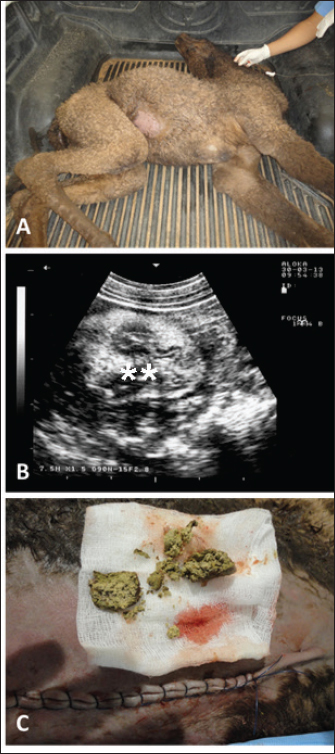

Fig. 2. Ultrasonographic findings in an adult female camel with a history of pica. The animal was admitted with a 7-day history of decreased fecal output and abdominal distension (A). Image (B) shows an obstructing foreign body occluding the small intestines partially (stars) using a 3.5 MHz sector transducer.

Fig. 3. Ultrasonographic findings in a 30-day camel calf with a history of pica. The calf was admitted with a 5-day history of no defection and abdominal distension (A). Image (B) shows an obstructing enterolith occluding the small intestines (stars) using a 7.5 MHz sector transducer. Image (C) shows the obstructing enterolith detected at right-sided surgical laparotomy.

Sonographic and postmortem findings are summarized in Table 2. In cases of camels presented with a history of pica and with decreased or total absence of feces, the obstructing foreign body was imaged in 10 of the 25 camels (40%) occluding completely or partially the intestines that may be confirmed at abdominal surgery (Figs. 2, 3, and 6). Foreign bodies within the rumen could not be visualized with ultrasound owing to the gas content. In cases where the rumen is impacted by sand, small pin-points revealing acoustic enhancement were imaged in 5 (20%) of the camels. An example of these cases is shown in Figure 7. Foreign bodies were removed from the rumen or intestines at exploratory rumenotomy and laparotomy, which included plastics, cloths, sand, mud, robes, wool balls, glasses, or even metallic objects that were blunt or sharp (Figs. 8 and 9).